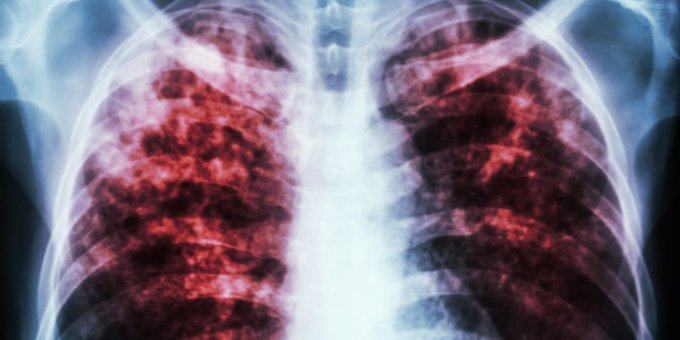

La tuberculosis suele atacar los pulmones, pero puede también dañar otras partes del cuerpo. Entérate aquí ow.ly/3k3w50xWVYB